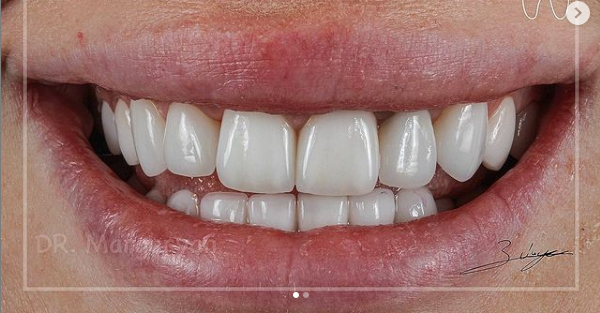

12 работ в портфолио

Маргарян Эдуард Вадимович принимает в МЕДИЦИНСКОМ СТОМАТОЛОГИЧЕСКОМ ЦЕНТРЕ НА ЗЕЛЕНОГРАДСКОЙ в Москве. Стаж 13 лет. Специализируется на ортопедии. Имеет 12 работ до/после в портфолио. Для уточнения дополнительной информации о специалисте или записи на прием можно позвонить по телефону

Установка керамических виниров

Установка виниров E-max